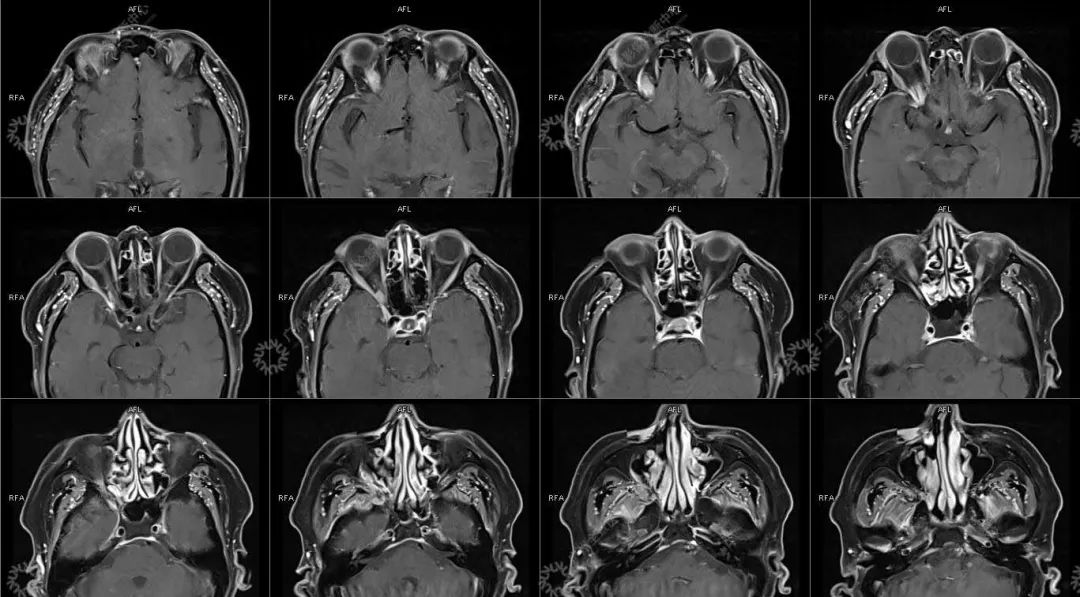

主诉:视力下降 2 年

现病史:双眼部隐痛、流泪,视力下降 2 年

结合影像及实验室检查,临床最终考虑 IgG4 相关性疾病。

●受累器官常表现为弥漫性或局限性肿大或形成肿块, 易误诊为恶性肿瘤